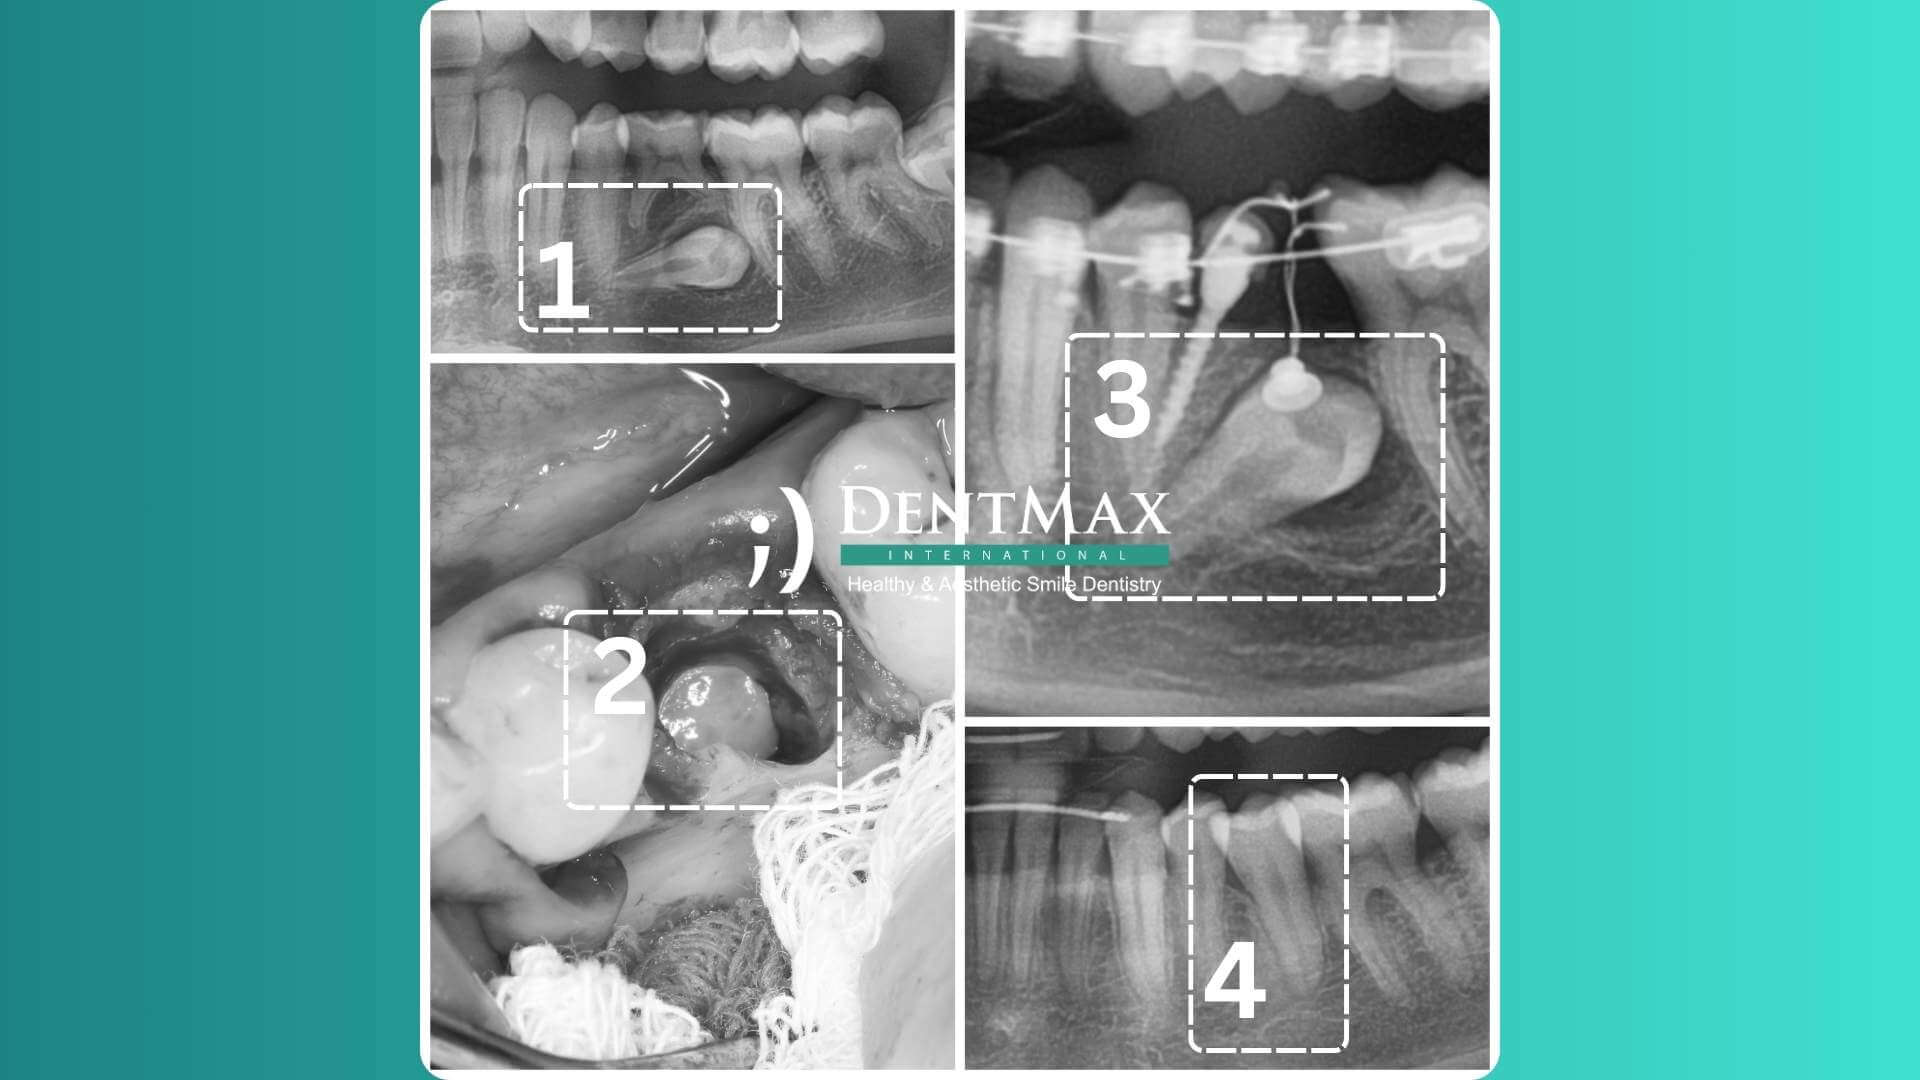

Tratamiento de Caninos Impactados

Tratamiento de Caninos Impactados: Todo lo que Necesitas Saber

Un canino impactado es un canino que no logra emerger en la boca en el momento esperado y permanece atrapado en el hueso de la mandíbula. Generalmente, después de los terceros molares, los caninos son los más frecuentemente impactados. Son dos veces más comunes en mujeres que en hombres y se encuentran generalmente en la mandíbula superior.

Cómo Detectar un Canino Impactado?

Un ortodoncista puede detectar dientes caninos impactados utilizando radiografías periapicales, radiografías panorámicas o tomografía computarizada de haz cónico. Un diagnóstico temprano es crucial, y se recomienda el primer examen ortodóntico entre los 6 y 7 años.

Cómo se Realiza el Tratamiento de los Dientes Impactados?

Un diagnóstico temprano e intervención son los enfoques más deseables para los dientes impactados. Sin un examen ortodóntico, un diagnóstico temprano es difícil. Ideas erróneas como "los tratamientos ortodónticos solo se pueden realizar después de los 12-13 años" retrasan el tratamiento. La ortodoncia moderna rechaza esta creencia obsoleta, destacando la importancia de un control temprano. Los exámenes ortodónticos se recomiendan anualmente para los niños en edad escolar primaria. Los métodos de tratamiento varían según los grupos de edad:

• Etapa temprana (7-11 años): Creación de espacio ortodóntico y expansión del arco.

• Etapa tardía (12 años en adelante): Exposición quirúrgica y tratamiento ortodóntico para guiar el diente a la posición correcta.